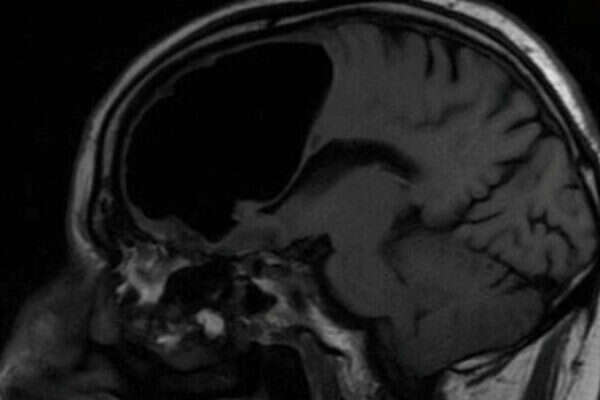

כיס האוויר בראשו של החולה // צילום: טוויטר, BMJCaseReports

הסריקות שביצעו בראשו של החולה גילו ממצא יוצא דופן – כיס אוויר בגודל של 3.5 אינץ' (8 ס"מ). התופעה, המכונה "פנאומטוקל", מתרחשת באונה המצחית, האחראית בין היתר על ביצוען של תנועות גוף.

בסריקת ה-MRI של הפציינט נמצא גם גידול שפיר קטן שגורם לאוויר להיכנס אל תוך מוחו. "זה כמו בבקבוק קולה – לפעמים יש שסתום חד כיווני שמאפשר לאוויר להיכנס ולא לצאת", הסביר ד"ר אלאן כהן, רופא נוירוכירוגי שלא היה מעורב באירוע המדובר.